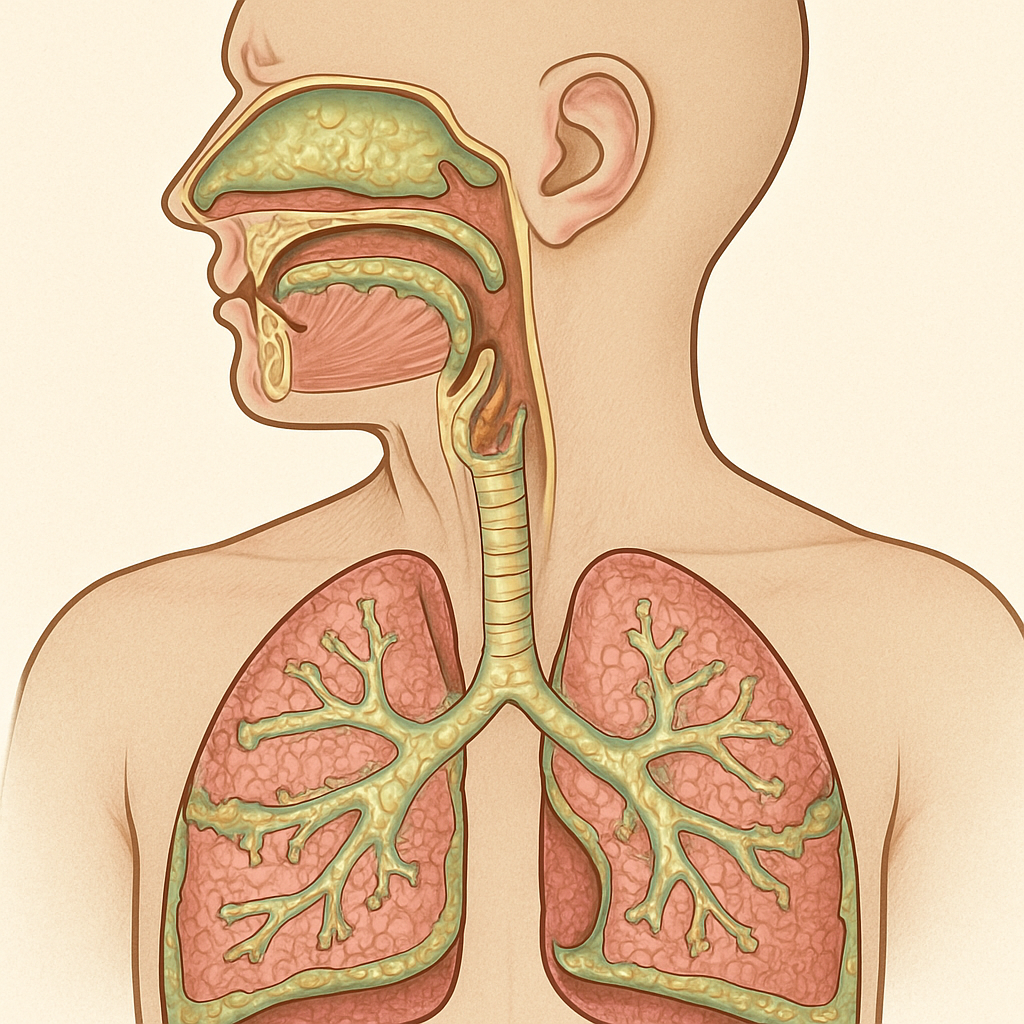

Por Qué Tu Garganta Produce Tanto Moco

La Verdad Sobre la Función Protectora

Antes de declarar la guerra a tus flemas, necesitas entender algo fundamental: tu cuerpo produce hasta 1.5 litros de mucosidad diariamente, y esto es completamente normal. Según los Institutos Nacionales de Salud, la mucosidad actúa como una “cinta transportadora” que atrapa polvo, bacterias y otros contaminantes antes de que lleguen a tus pulmones.

El problema surge cuando este sistema se sobrecarga o se altera. Dr. Andrew Lane, experto en otorrinolaringología de Johns Hopkins, explica que “cualquier cosa que respire queda atrapada en la mucosidad, como en papel matamoscas. En la próxima hora, inhalará miles de bacterias, pero nunca lo sabrá porque su sistema mucoso las atrapó”.